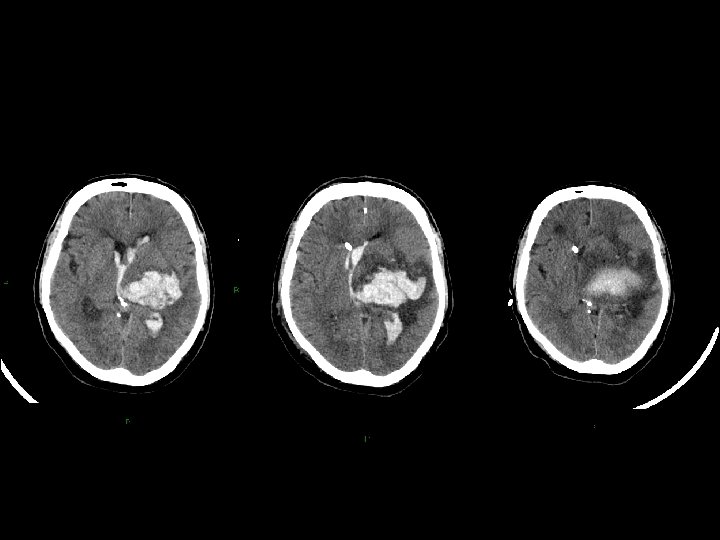

Stato vegetativo • giace, apparentemente incosciente, anche ad occhi aperti; • presenta funzioni cardiocircolatorie e respiratorie, termoregolazione, funzioni renali e gastrointestinali conservate; • non necessita di tecnologie di supporto; • mostra, alla TC e alla RMN, segni più o meno marcati di danno focale o diffuso; • presenta alla SPECT gradi variabili di riduzione sovratentoriali di perfusione cerebrale; • evidenzia, alla PET, variabile topografia e gradi variabili di riduzione del metabolismo del glucosio; • mostra alterazioni variabili dell’attività EEG.